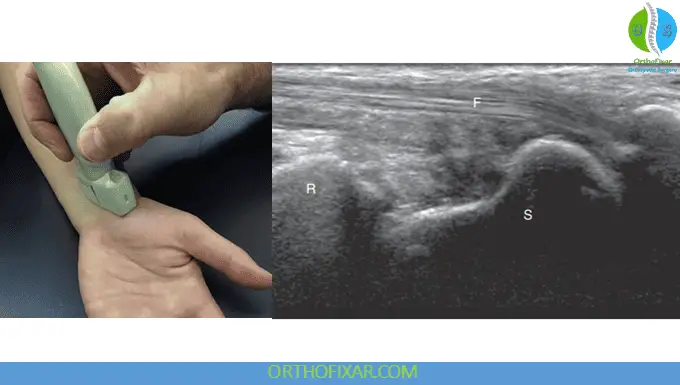

The radial side of the anterior wrist provides access to several important structures. With the transducer positioned in long axis lateral to the median nerve, the flexor carpi radialis can be observed attaching to the second and third metacarpals. In this plane, the tendon exhibits a hypoechoic appearance with a characteristic fibrillar pattern.

Bony Landmark Identification: The distal radius and scaphoid appear as hyperechoic bone contours. Clear visualization of the scaphoid surface allows detection of irregularities that may indicate fracture, making ultrasound a valuable tool for acute trauma assessment.

Vascular Structures: In short axis orientation, the radial artery and vein can be identified just radial to the flexor carpi radialis tendon, providing important information about vascular integrity.